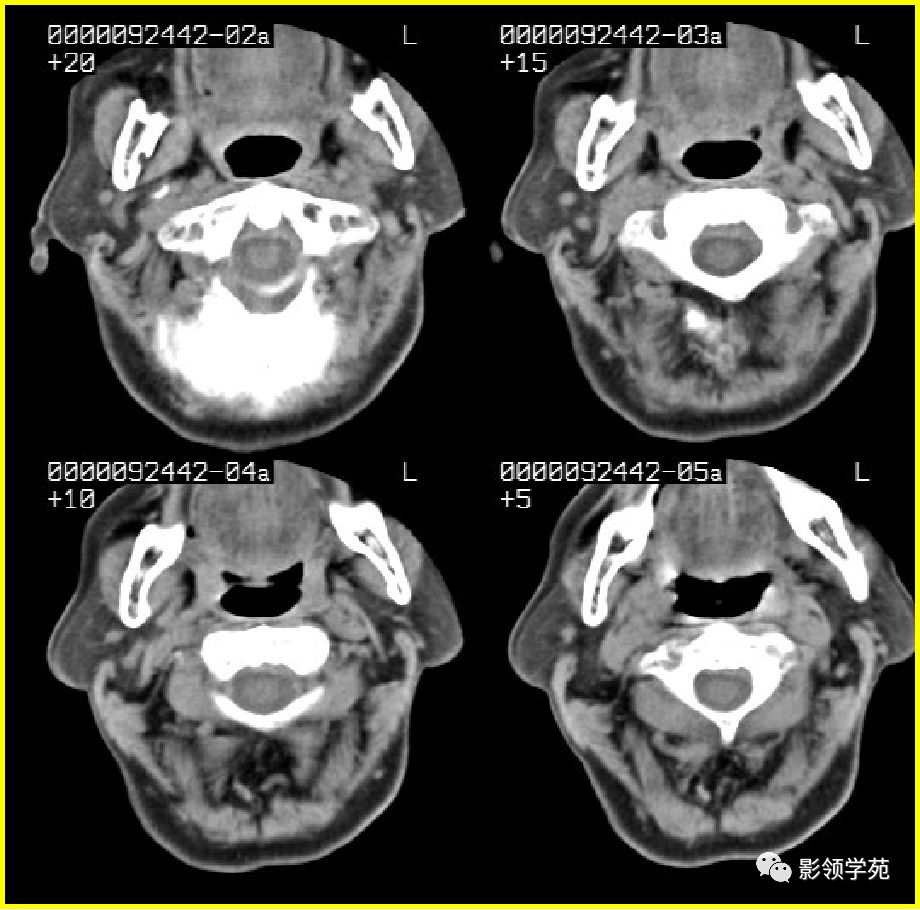

腮腺解剖

- 位于下颌骨后,胸锁乳突肌前,上致颅底,位于乳突尖和颞颌关节之间,下至下颌角,是茎突前咽旁间隙重要器官

- 腮腺是脂肪性腺体,CT呈低密度

- 腮腺内血管显示清楚